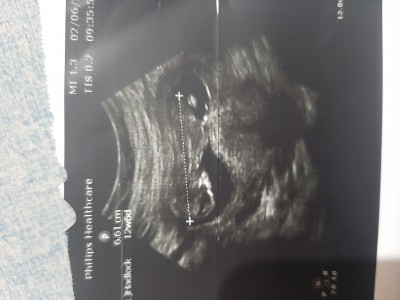

Cinsiyet tahmini yapar mısınız  lutfennnn cok merak ediyorum

Gebelik haftası 15+2

Erkek gibi duruyor ama Dr ne dedi merak ettim?

Doktor erkek dedi ya %80

Aslında 15.hafta da da gözükür ama net konuşur normalde o tarihte bence kız da olabilir erkek olsa 15.haftada artık organı tam net olmuş olması gerekir diye düşünüyorum. Tabii tıbbi bir bilgi değil sadece yorum :)